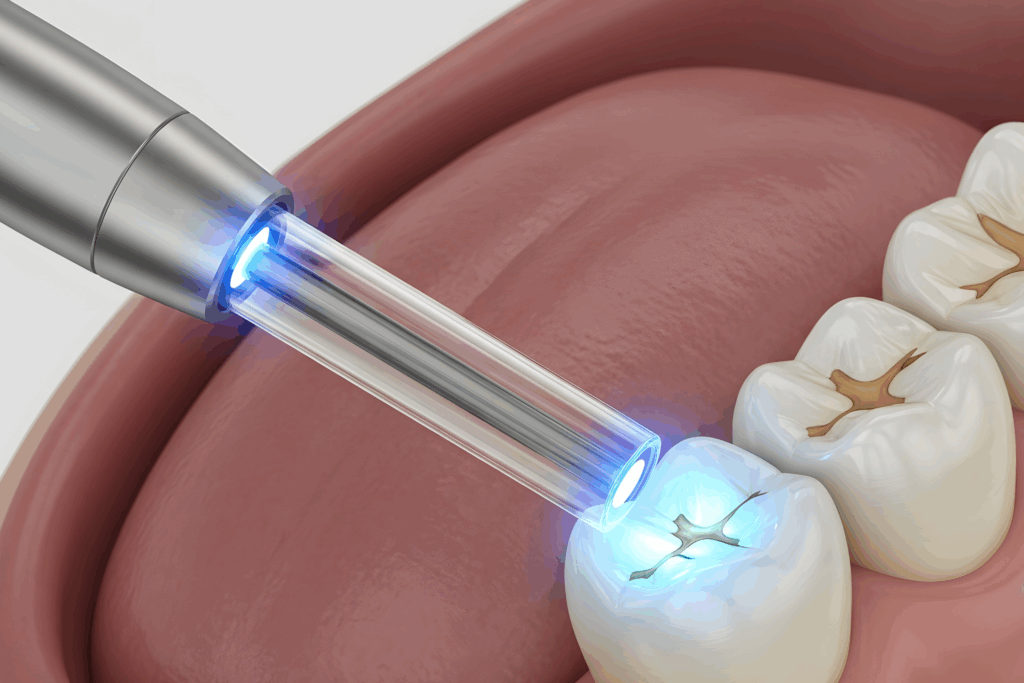

ここまで読んで、「じゃあ、どうすれば虫歯の再発を防げるのだろう?」と思われた方も多いでしょう。その答えの一つが、当院がすべての虫歯治療で実践している『コーティング法』という新しい治療手法です。

虫歯を削った後の歯の表面は、いわば『むき出しのコンクリート』のような、非常にデリケートで無防備な状態です。この表面は、肉眼では見えない微細な凹凸や亀裂が無数に存在し、細菌が付着・侵入しやすい状態になっています。

従来の治療では、この無防備な状態の上に、セメントを介して銀歯や詰め物を『置く』だけでした。これでは、セメントが劣化すれば、すぐに隙間ができてしまいます。

しかし、『コーティング法』は全く発想が違います。

虫歯を取り除いた後の無防備な歯の表面を、特殊な高機能材料で一層、完全に覆い尽くし、バリア(保護膜)を作ってしまうのです。これは、スマートフォンの画面に保護フィルムを寸分の狂いなく貼り付けるイメージに近いかもしれません。

この一層のコーティングが、以下のような絶大な効果を発揮します。

- 細菌の侵入経路を完全に遮断: 歯と詰め物・被せ物の間を完璧に封鎖(シール)するため、虫歯菌が内部に侵入する物理的な隙間がなくなります。

- 歯の強度を高める: 歯と一体化することで、削って弱くなった歯の強度を補い、歯が割れる(歯牙破折)リスクを低減します。

- 詰め物・被せ物の接着力を最大化: コーティング層が強力な接着ハブとして機能し、その上に装着するセラミックなどの詰め物・被せ物が、まるで元々一つの歯であったかのように強固に一体化します。

この処置を行うかどうかで、治療後の歯の寿命は数倍、十数倍変わると言っても過言ではありません。